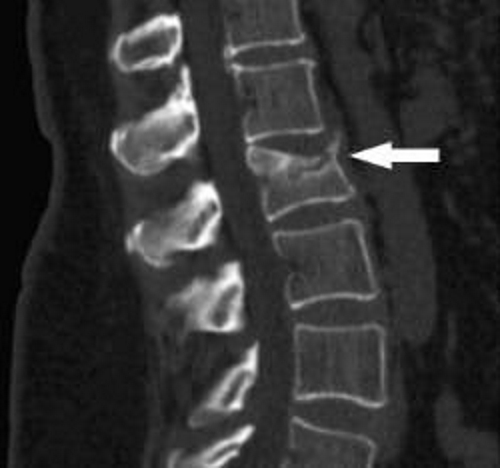

Компьютерная томография. Это более точный и дорогостоящий вариант рентгенографии.

МРТ (магнитно-резонансная томография). Это самый точный метод диагностики заболеваний позвоночника, который позволяет определить степень разрастания остеофитов с точностью до миллиметра. МРТ обеспечивает быстрые результаты и минимальное облучение для пациента.

Для диагностики спондилоартроза врачи могут использовать рентгенографию, магнитно-резонансную томографию (МРТ) или компьютерную томографию (КТ). Эти методы помогают визуализировать изменения в позвоночнике и оценить степень заболевания.